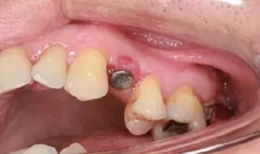

從圖1可以看出患者缺牙區(qū)的間隙充足,牙齦健康,頰側(cè)軟組織略有凹陷。

圖1 缺牙區(qū)的頰側(cè)和口內(nèi)照片